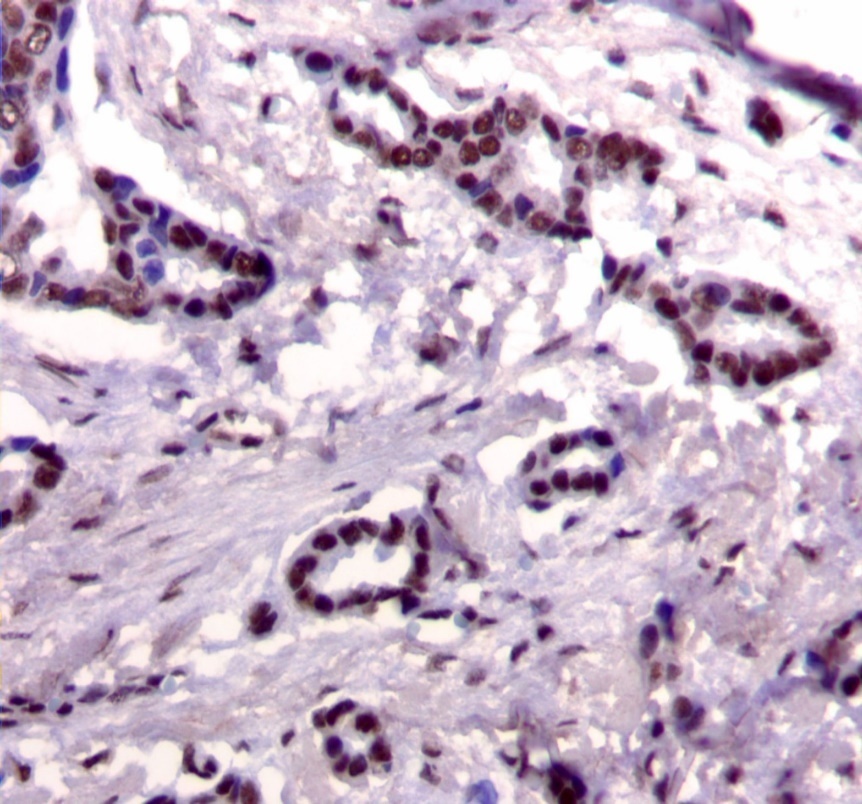

Figure 1.Nuclear staining pattern for IRS-1. (IRS-1 immunohistochemical stain, 200x magnification)

We used the following histologic criteria for IRS-1 and IRS-2 staining patterns which are outlined in a previous study.13 For IRS-1, a nuclear pattern was defined as diffuse nuclear staining (Figure 1). IRS-2 staining patterns were defined using the following criteria: Diffuse cytoplasmic staining was defined as evenly distributed cytoplasmic reactivity (Figure 2); punctate cytoplasmic staining was defined as clearly demarcated puncta of staining within the cytoplasm (Figure 3); and membrane staining was defined as focal or diffuse membranous staining (Figure 4). Sections of normal pancreas and normal breast tissue were used for positive and negative controls. The pathologists assessing staining patterns were blinded to the tumor recurrence score and all other data at the time of assessment.